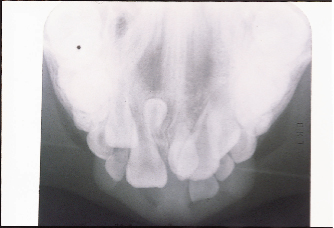

Hình 8: X-quang quanh chóp của odontoma tổng phức hợp |

Hình 10: Sư tiêu xương chân răng của răng cửa giữa và bên hàm trên gây ra bởi odontome đa hợp trong hình minh họa 9 |

Bệnh lý học

Sự hình thành nang thân răng (Dentigerous cyst ) là một vấn đề khác có thể liên quan đến các răng dư (Hình 9), Primosch báo cáo túi nang mở rộng ở 30% các trường hợp, nhưng bằng chứng mô học của sự hình thành u nang đã được tìm thấy trong chỉ 4 đến 9% của các trường hợp. Sự tiêu xương của chân răng dư liền kề có thể xảy ra nhưng nó là vô cùng hiếm (Hình 10)